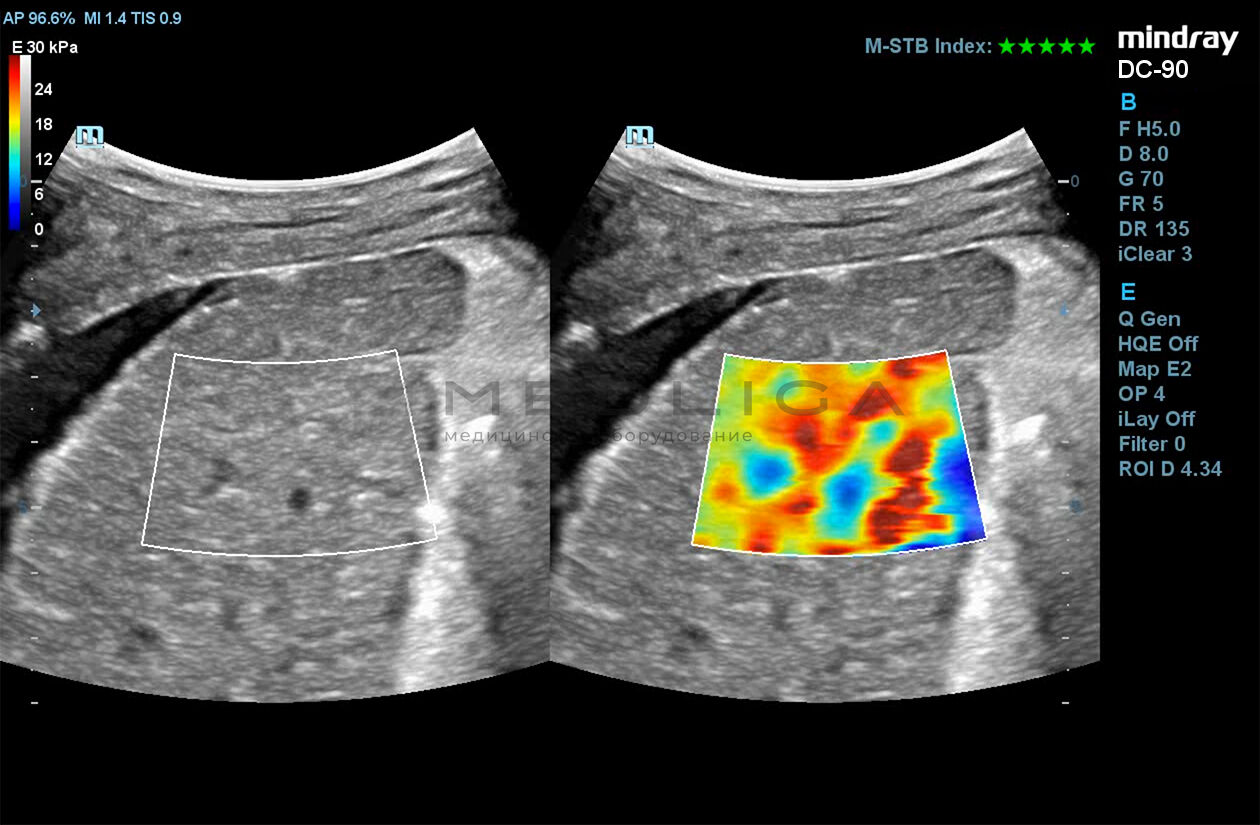

STE (Sound Touch Elastography)

STE интегрирована с эксклюзивной технологией Ultra-Wide Beam Tracking от Mindray для двумерной эластографии сдвиговой волной в реальном времени. Специализированные измерительные инструменты позволяют проводить количественный анализ модуля упругости с высокой точностью.

- на линейных датчиках

- на конвексных датчиках